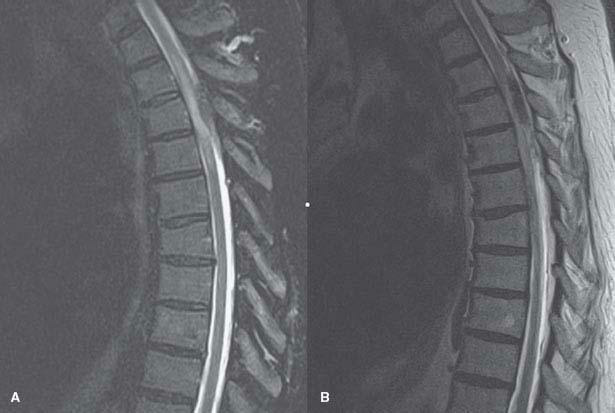

1. A 70-year-old man complains of back pain, lower extremity weakness, and sensory deficit to all modalities below his mid-abdominal region for the past 3 days. Since onset, his neurologic manifestations have progressed rapidly such that he is paraplegic on the day of evaluation. His MRI is shown in Figure 11.2. The most important risk factor for this patient’s condition is:

FIGURE 11.2 (A) Sagittal STIR MRI; (B) sagittal T2-weighted MRI

Figure 11.2 shows an epidural collection consistent with an epidural hematoma. The most common initial symptom is back pain, followed by development of a myelopathic syndrome as the hematoma compresses the cord. It is more common in males and more frequent in the thoracolumbar region. Major risk factors for spinal epidural hematoma include anticoagulation either from medications or from coagulopathies and thrombocytopenia. Other factors that may increase the risk of this condition are trauma, neoplasms, pregnancy, and vascular malformations.

Dural arteriovenous fistula is the most common vascular malformation of the spinal cord, and presents with an insidious and slowly progressive myelopathic syndrome, sometimes with acute exacerbations. These manifestations are caused by increased venous congestion and mass effect in the spinal cord, leading to venous infarcts. Acute hemorrhages may occur; however, dural arteriovenous fistulas rarely produce epidural hematomas. MRI of the spine may show cord signal abnormalities and flow voids, but the definitive diagnostic procedure is conventional angiography.

Atherosclerosis, aortic dissection, and aortic manipulation (especially above the renal arteries) are associated with ischemic infarcts of the spinal cord. Prolonged hypotension may be associated with watershed infarcts of the spinal cord. Hypotension, atherosclerosis, and aortic manipulation are not typically associated with spinal epidural hematomas.